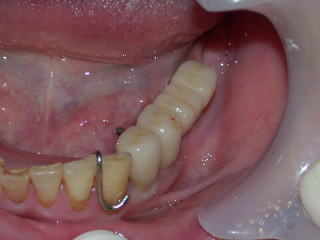

平成20年3月、上部構造物4本を装着しました。

舌側面観です。

歯肉の状態は前回型取り時より平坦化して、炎症も治まりつつあります。

咬み合わせの状態をチェックし、装着します。

次回、セメントが完全硬化後、再度咬み合わせなどををチェックし、歯間ブラシを主にブラッシング指導を行います。

セメントが充分硬化した翌日、インプラント周囲を主にしての歯ブラシ指導に来てもらいました。

歯ブラシだけでは良く磨けないので、歯間ブラシを併用して、衛生的に保ちます。